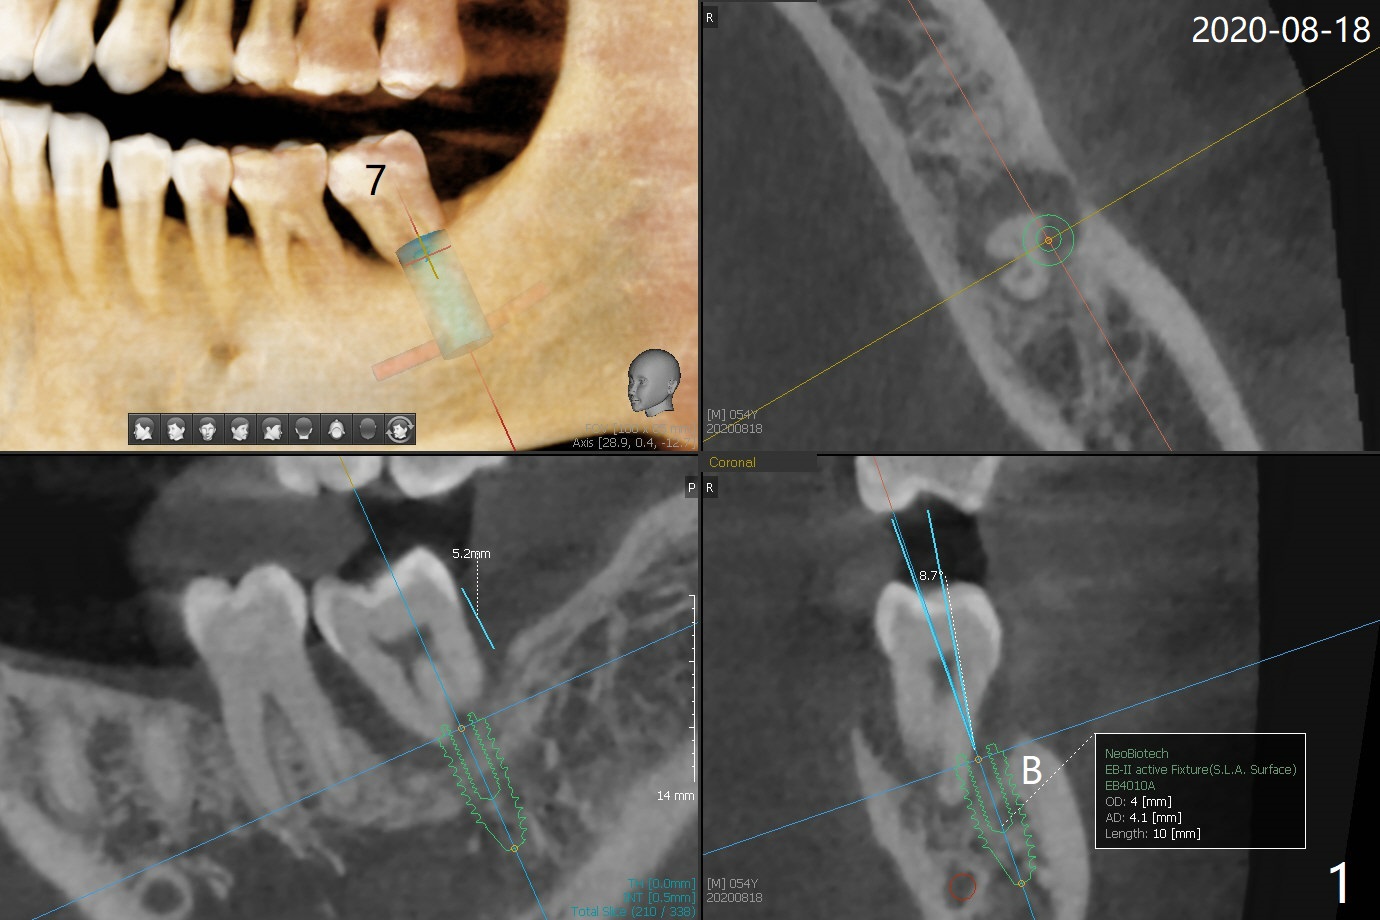

54岁男右下6,7拔除,延期种植十个月还没有完成,左下7松动(图一,二),准备即刻种植,有4-5毫米根尖骨质固定植体(图三,四),缩短治疗时间,但是必须逾越神经管,需要导板,植入偏细植体(4毫米),这样有2毫米安全地带(图四),为了减少植体过细造成植体断裂,使用五级钛植体。由于植体种得深,牙龈厚,基台袖需要长4或者5毫米(图三:粉红色),试用治疗性基台(4.5x4,4.5x15 degree A or B, 4mm),可能需要使用带角度基台(图四:蓝色),这样避免坚硬颊侧骨板,颊侧多放些粘性骨粉。第二次取模后,固定松动牙,让病人舒服些,之后必须调整咬合。